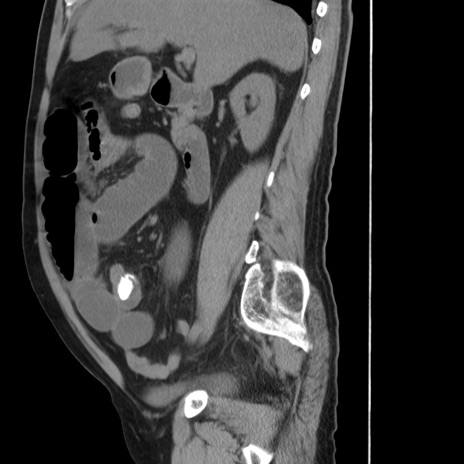

冠状断像

【症例】 60歳代男性

【主訴】 腹部膨満、嘔吐

【現病歴】5日前頃より倦怠感を認め食事量減少し4日前の朝嘔吐、食事摂取困難となった。 3日前近医受診し点滴施行され整腸剤などを処方された。 当日他院を受診し、腹部膨満著明、炎症反応の上昇(CRP10.8、WBC11200)あり、紹介受診となる。

【身体所見】 意識JCS1 受け答えがはっきりしないBP 111/57mHg、 P 67bpm、、BT35.2°C、SpO2 97%(RA)、 腹部:膨隆、打診で鼓音あり、全体的に圧痛有り、腸蠕動音(-)、反跳痛ははっきりせず。

【データ】WBC 11400、CRP 14.20